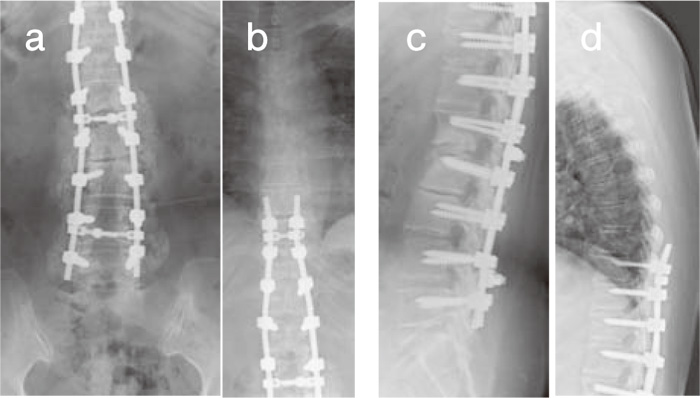

Fig.5

X-ray films after second surgery. Decompression at L1-2 with instrumentation and local bone grafting at T9-L5 was performed. a and b: anterior-posterior view. c and d: profile view.